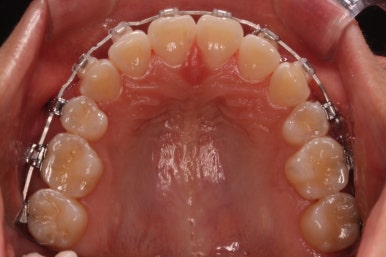

다시 이번 환자분으로 돌아가, 입 안모습을 보시겠습니다.

부산무턱교정 키다리아저씨치과에서 처음 내원하셨을 당시의 입 안의 모습입니다.

아래턱이 작아서 상대적으로 윗니들이 많이 돌출되었고, 뻐드러져 있습니다. 윗니들이 배열되어 있는 형태도 V자에 가깝게 입천장이 좁은 양상입니다.

틈은 다 다물어졌고, 부가적인 정교한 마무리 과정을 더 거치게 됩니다.

중앙선도 잘 맞고 교합도 잘 마무리되었습니다.

이 뽑은 자리가 다시 벌어지지 않게 앞니가 다시 틀어지지 않게 유지철사를 부착하고 마무리를 하였습니다.

전후 비교해 보겠습니다.

중앙선, 교합, 뻐드러짐 모두 좋아졌고 이를 뽑고 교정했지만 발치 공간이 남지 않고 잘 마무리 되었습니다.